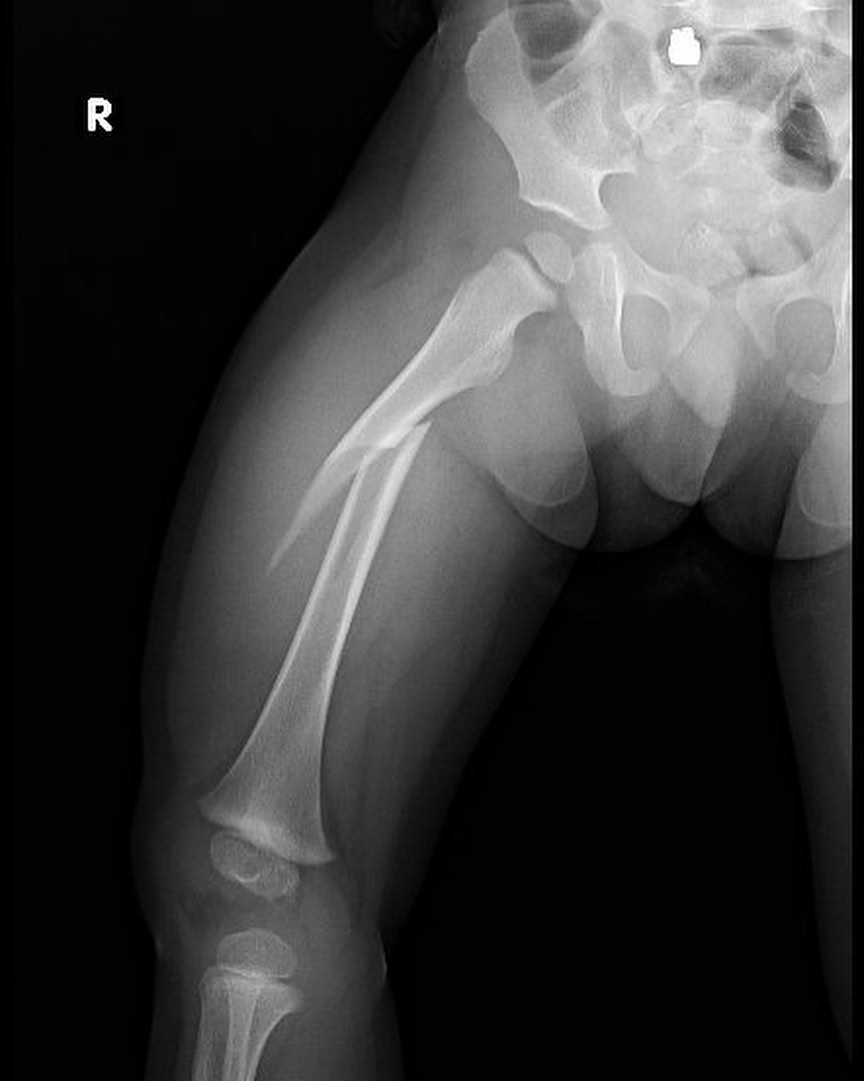

Fractura de fémur

El año pasado mi pacientito Dylan se fracturó el fémur, realizamos tratamiento conservador y ahora está al 💯 Vino a consulta y recibí este delicioso regalo, ¡muchas gracias Dylan!